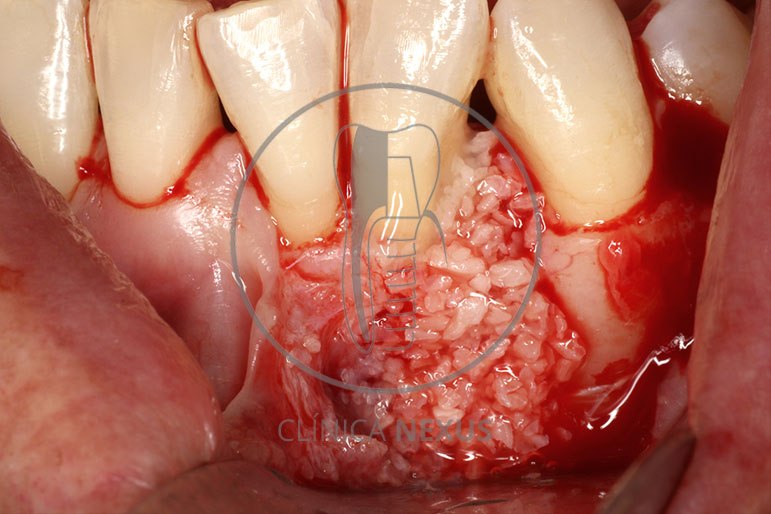

Tratamiento de defectos periodontales infraóseos en sector antero-inferior empleando gel de amelogeninas (Emdogain®) en combinación con un aloinjerto óseo (Biobank®). Paciente de 64 años, sin problemas médicos de relevancia, que presenta una periodontitis leve generalizada, pero asociada a presencia de defectos óseos verticales profundos a nivel de los espacios interdentales entre los caninos y los incisivos laterales inferiores. Tras la pertinente fase higiénica, se llevó a cabo una cirugía periodontal regenerativa, en la que, tras eliminar el cálculo subgingival (factor causal), se empleó una combinación de amelogeninas con un aloinjerto, para promover la regeneración tisular del periodonto perdido. Las imágenes clínicas y radiológicas, al año de seguimiento, reflejan un resultado terapéutico óptimo, con regeneración completa del tejido periodontal y mejora del pronóstico de los dientes involucrados.